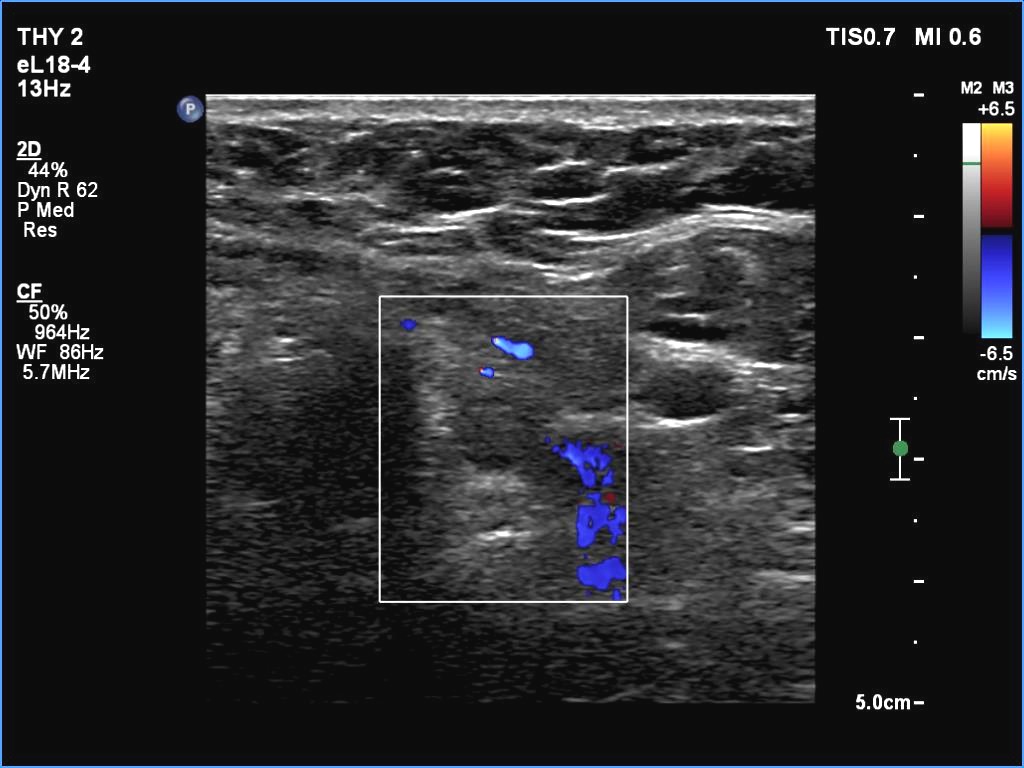

Lower pole of the left lobe, transverse scan, color Doppler mode. The nodule is avascular.